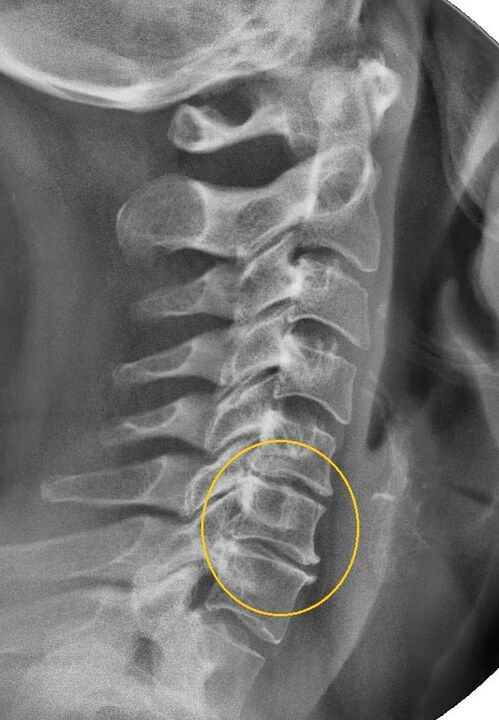

The most informative diagnostic procedure is radiography.Grade 1 pathologies correspond to radiological stage 1 or 2.The resulting images display the typical symptoms of the disease.

| X-ray stages of cervical osteochondrosis of the 1st degree | Characteristic signs |

|---|---|

| Stage 1 | Small changes in the curvature of the spine in the cervical region affect one or more segments |

| Stage 2 | Slight thickening of intervertebral discs, deformation of marginal processes, correction of lordosis, small growths of bone structures |